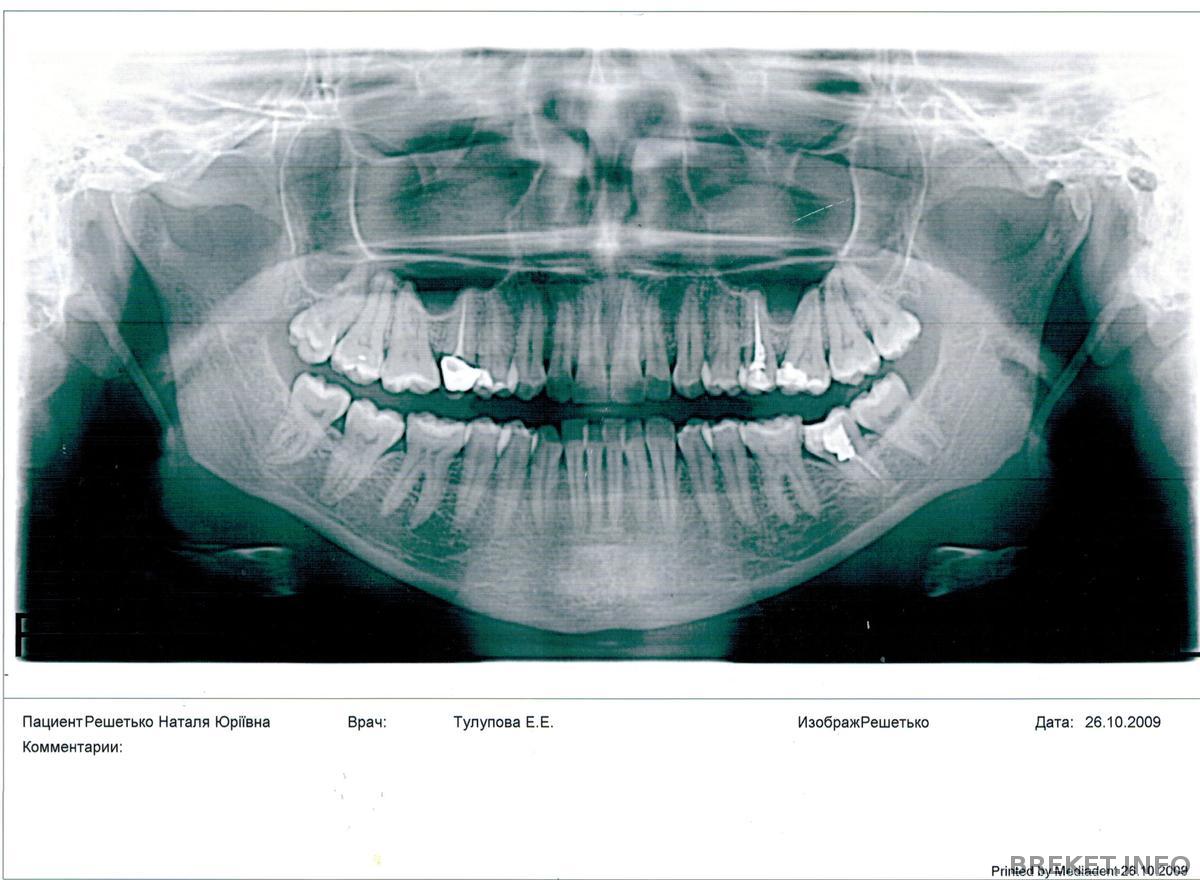

Всем привет) Я установила наконец бс, но ситуация у меня довольно непростая. Во-первых, это отсутствие большого кол-ва зубов, а точнее 7 штук. Испортились они во время беременности, тогда лечить не желательно было, потом недоглядела, вообщем удалила. Может какие-то из них и можно было спасти, даже и не знаю.

Теперь про брекеты. Зубы у меня не столько кривые, сколько разные по размеру, если сравнивать с аналогичными им. Вообщем брекеты мне поставили пока на вч, и вот что мне сказала ортша: т.к. с правой стороны отсутствуют 4, 5 и 7, будем двигать 8 и 6 на место 5 и 6 получается, а на место 4 имплант. Теперь с левой стороны: там у меня отсутствует 5, она хочет сдвинуть зубы на место этой пятерки, а 8 удалить, хотя зубов я и так много удалила, якобы их будет тяжело передвигать и чтобы была симметрия с двух сторон, т.е справа и слева по 6 зубов.

Вообщем меня это очень смущает, брекеты мне уже поставили, но она сказала 8 удалить к след.приему. Очень жаль мне этот зуб, тем более он здоровый. Я не знаю, можно ли оставить его, а справа просто поставить импланты на место 4 и 5, а 8 сдвинуть на место 7? Я не говорю о том, что и на нч она думает удалять мне 8 или нет

вот так выглядят мои зубы, в косую линию)